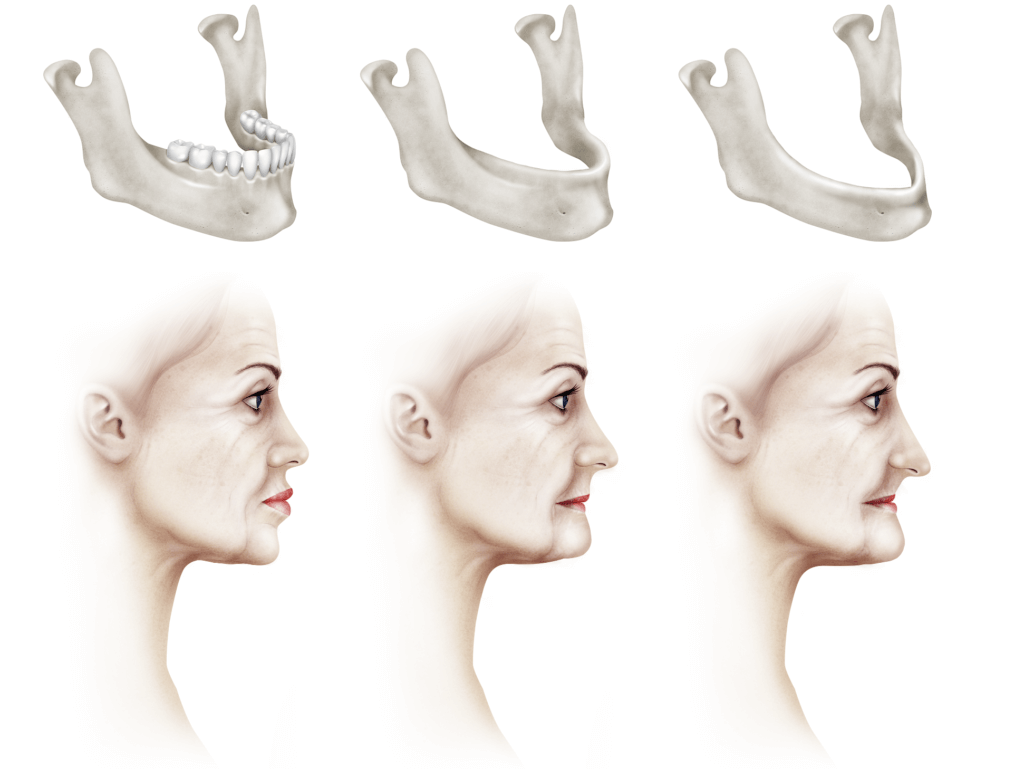

La razón es que los implantes dentales tradicionales son endoóseos, es decir, se colocan dentro del hueso maxilar o mandibular para anclar y/o estabilizar prótesis dentales. Por lo tanto, en los casos de gran reabsorción ósea, maxilares atróficos y, por ende, dimensiones disminuidas, no es posible colocarlos a menos que se realicen cirugías previas con técnicas complejas de regeneración ósea a través de injertos intra o extraorales para la colocación futura de implantes dentales endoseos. Esto prolonga el tiempo total de tratamiento para lograr una rehabilitación protésica dental, sometiendo al paciente a múltiples cirugías y aumentando considerablemente los costos.

Ahora, con la utilización de los implantes subperiósticos personalizados, la falta de hueso ya no será un impedimento, ya que se fabrican a la medida de cada paciente y se colocan rodeando la estructura ósea. Con una tecnología digital de vanguardia y un enfoque personalizado centrado en el paciente, se ofrece una alternativa efectiva y cómoda para aquellos que enfrentan desafíos de reabsorción ósea con dimensiones maxilares no óptimas.

Los implantes dentales subperiósticos personalizados surgen como una alternativa innovadora a los implantes tradicionales, especialmente beneficiosos en casos de atrofia ósea grave, es decir, cuando el hueso maxilar no tiene suficiente volumen para soportar implantes endóseos. A diferencia de los implantes endóseos que se insertan dentro del hueso, los subperiósticos se colocan sobre el hueso y se fijan con tornillos, lo que permite colocar prótesis dental el mismo día de la cirugía en la mayoría de los casos. Estos implantes se recomiendan para:

- Resultados estéticos: Permiten una mejor estética facial al evitar la reabsorción ósea y la pérdida de volumen en el área de las encías, traduciéndose en una sonrisa más natural y atractiva.